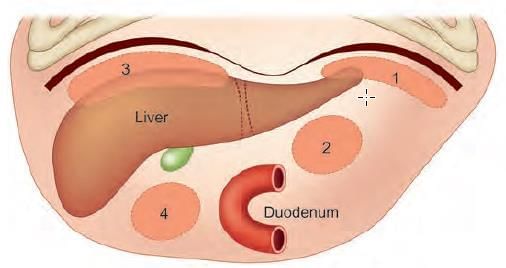

In CT scan of liver, identify the arrow marked segment: (INI-CET Nov 2022)

Match the location of vermiform appendix with the labelling given in the diagram: (INI-CET May 2023)